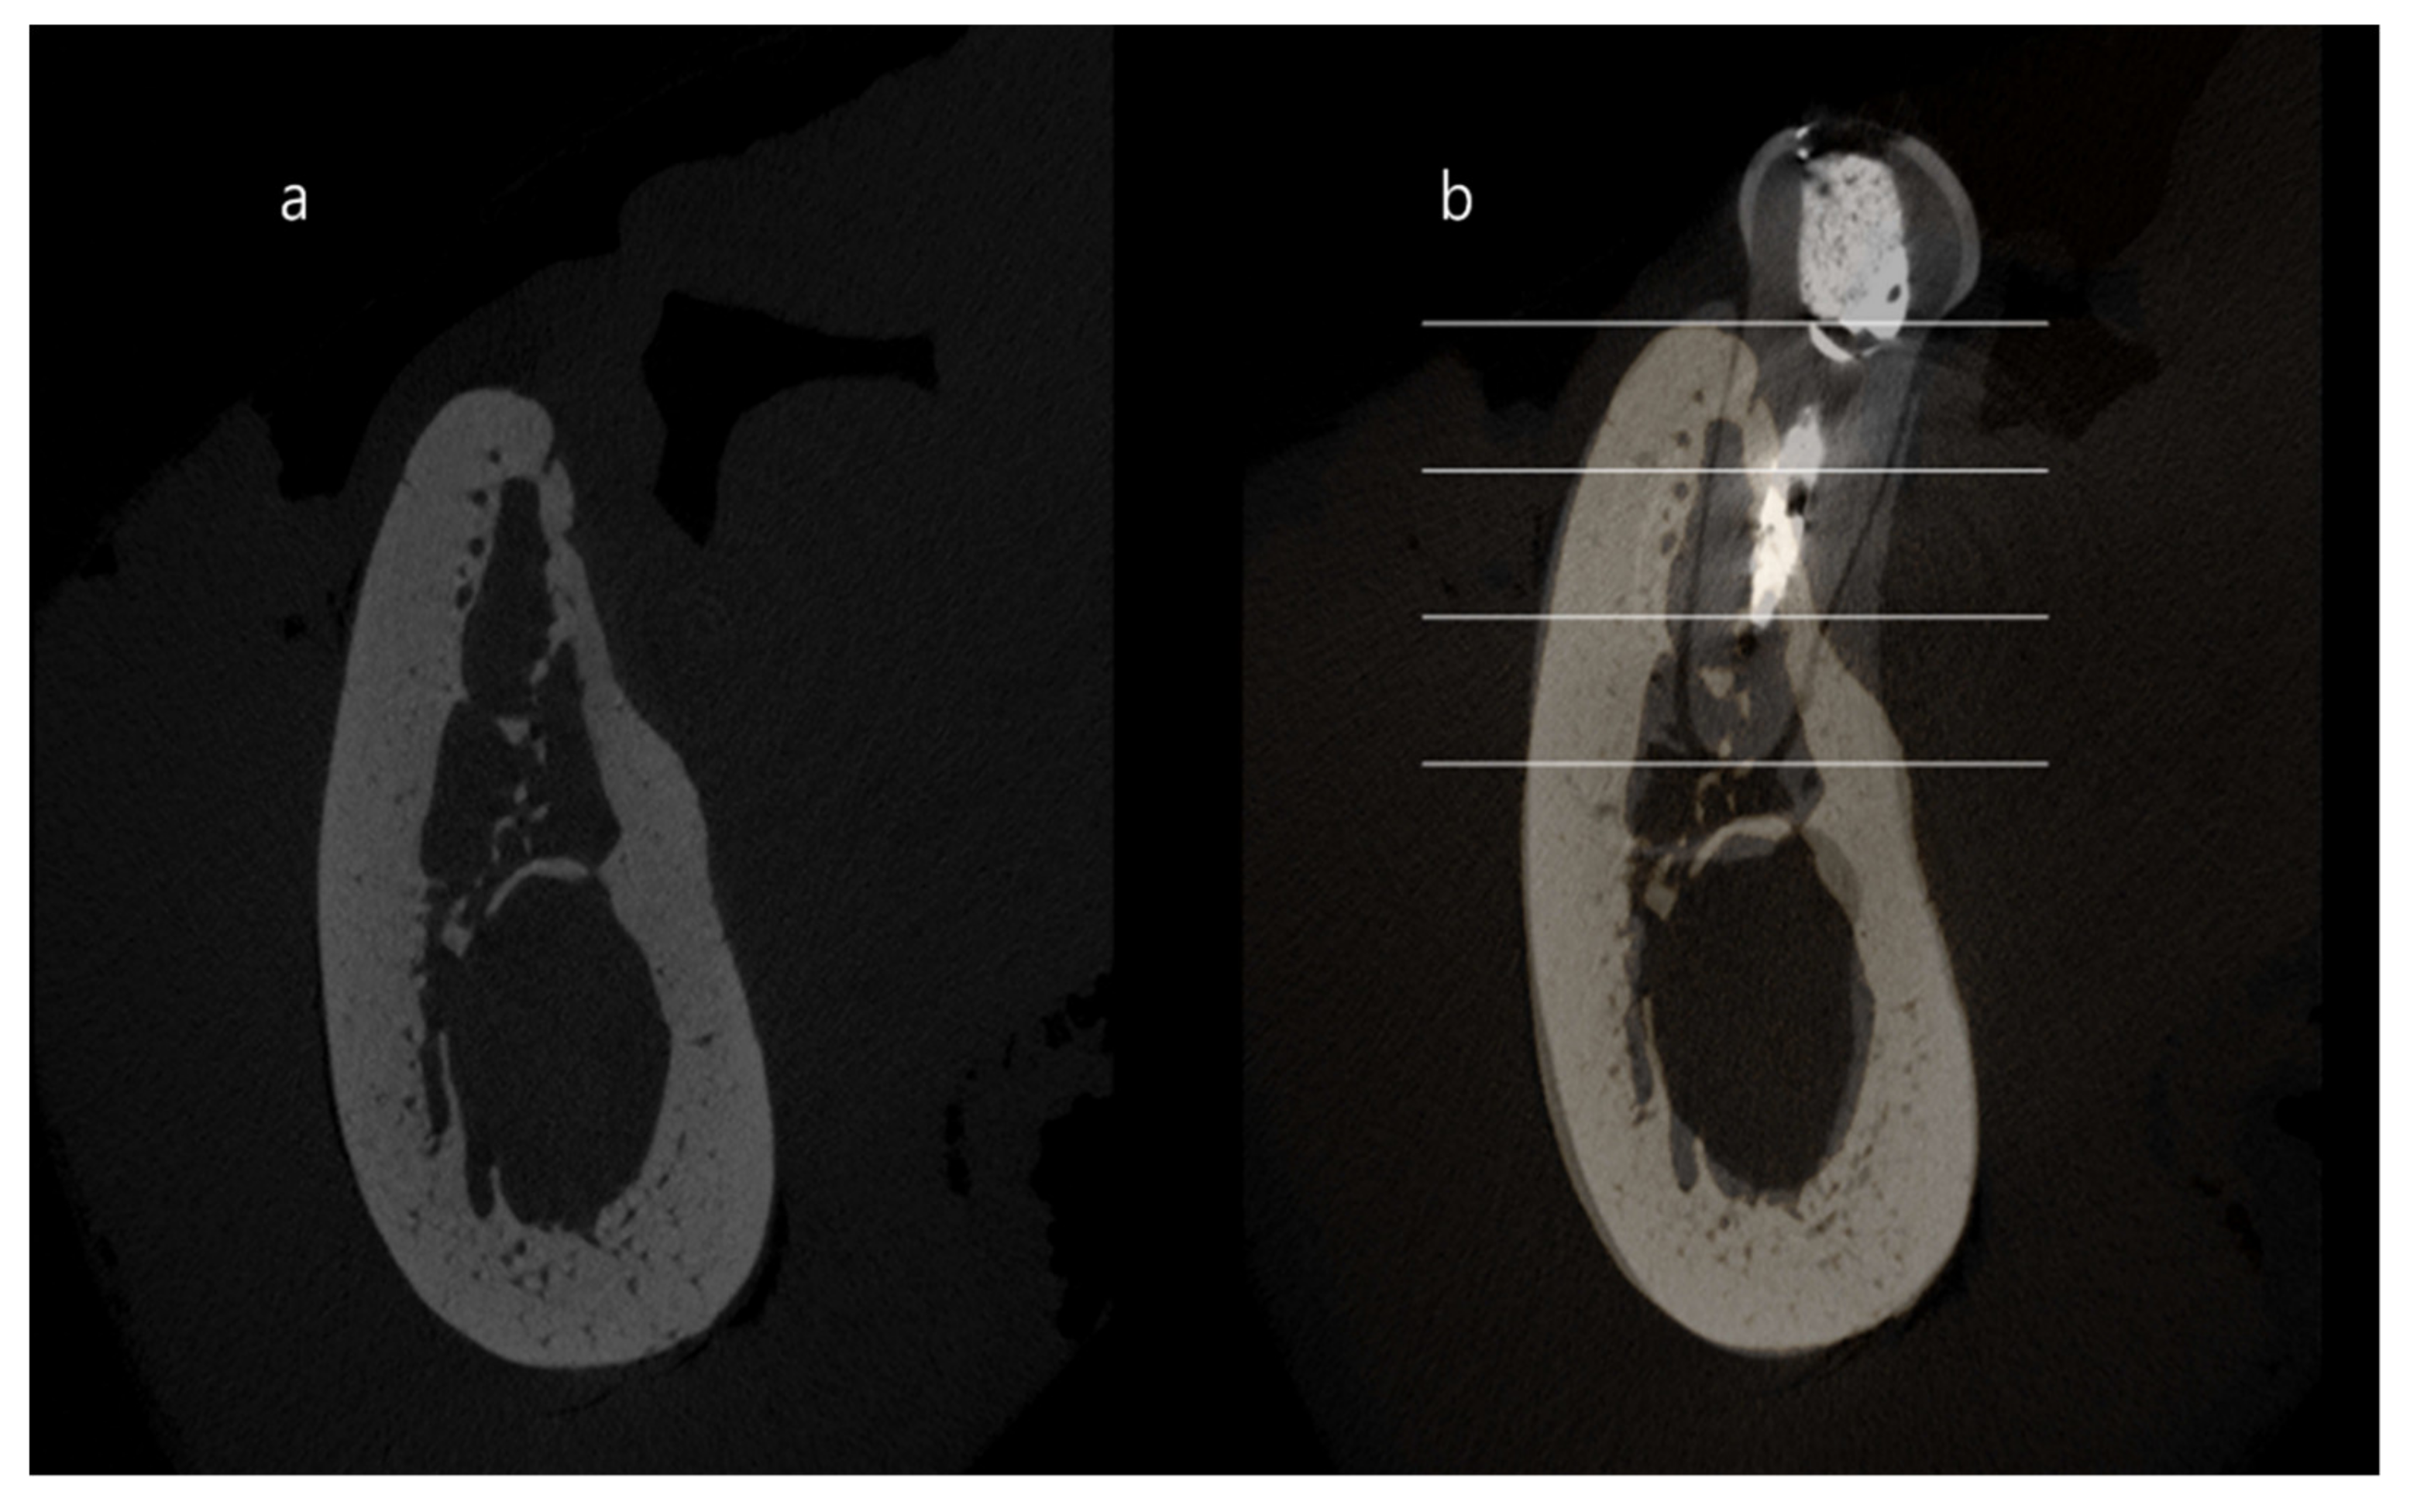

2.7. Quantitative Analysis of the Superimposed Micro-CT Images

The residual root of each distal site was used as a reference alveolar ridge when calculating the ridge contraction. To investigate the change after tooth extraction and/or ridge augmentation, each middle section of the mesial root was superimposed with reference sections (distal root) as previously described [6,11]. The area was demarcated into three regions at each superimposed image: coronal 1/3, middle 1/3 and apical 1/3, and then the dimensional changes of the experimental area compared to the reference area were calculated and expressed as percentages in these three areas (Figure 4).

Figure 4. Buccolingual micro-computed tomography images. (a) extraction socket of mesial root area and (b) superimposition of extraction socket (mesial) area and distal root. The area was divided into three areas, with coronal, middle and apical regions.